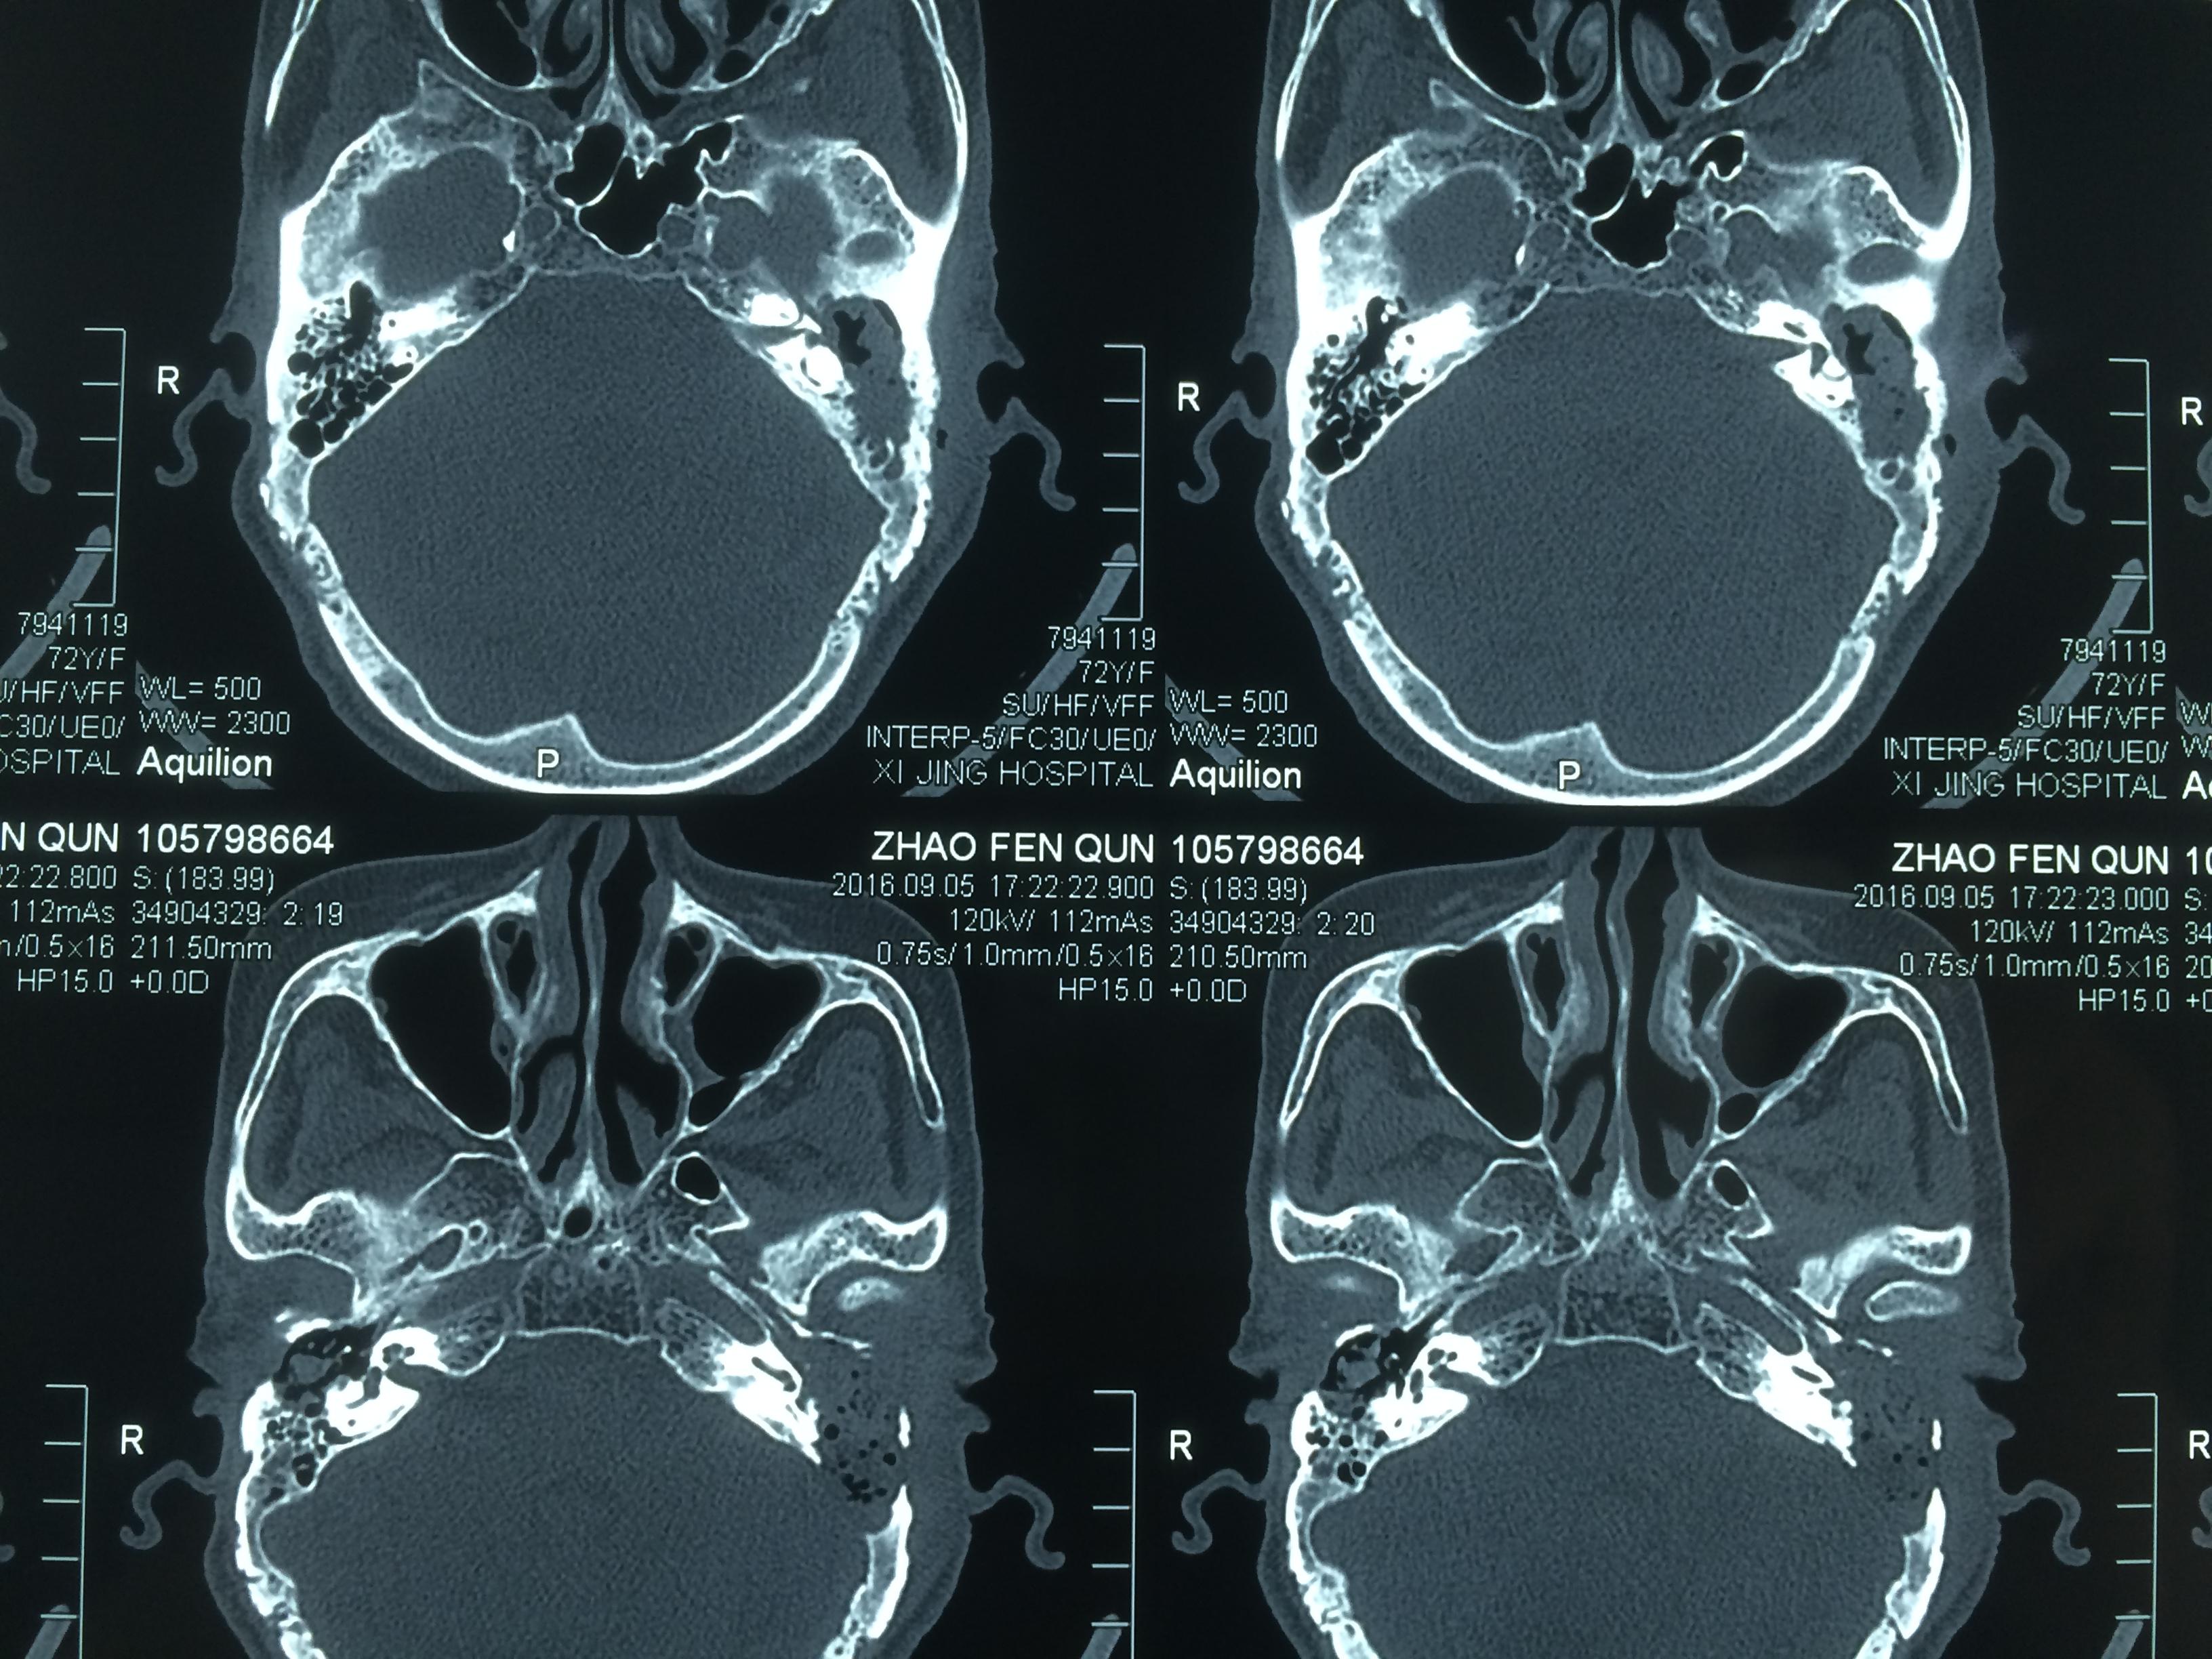

胆脂瘤ct图片

图中箭头所指灰色部分为中耳胆脂瘤

胆脂瘤型中耳炎的ct表现